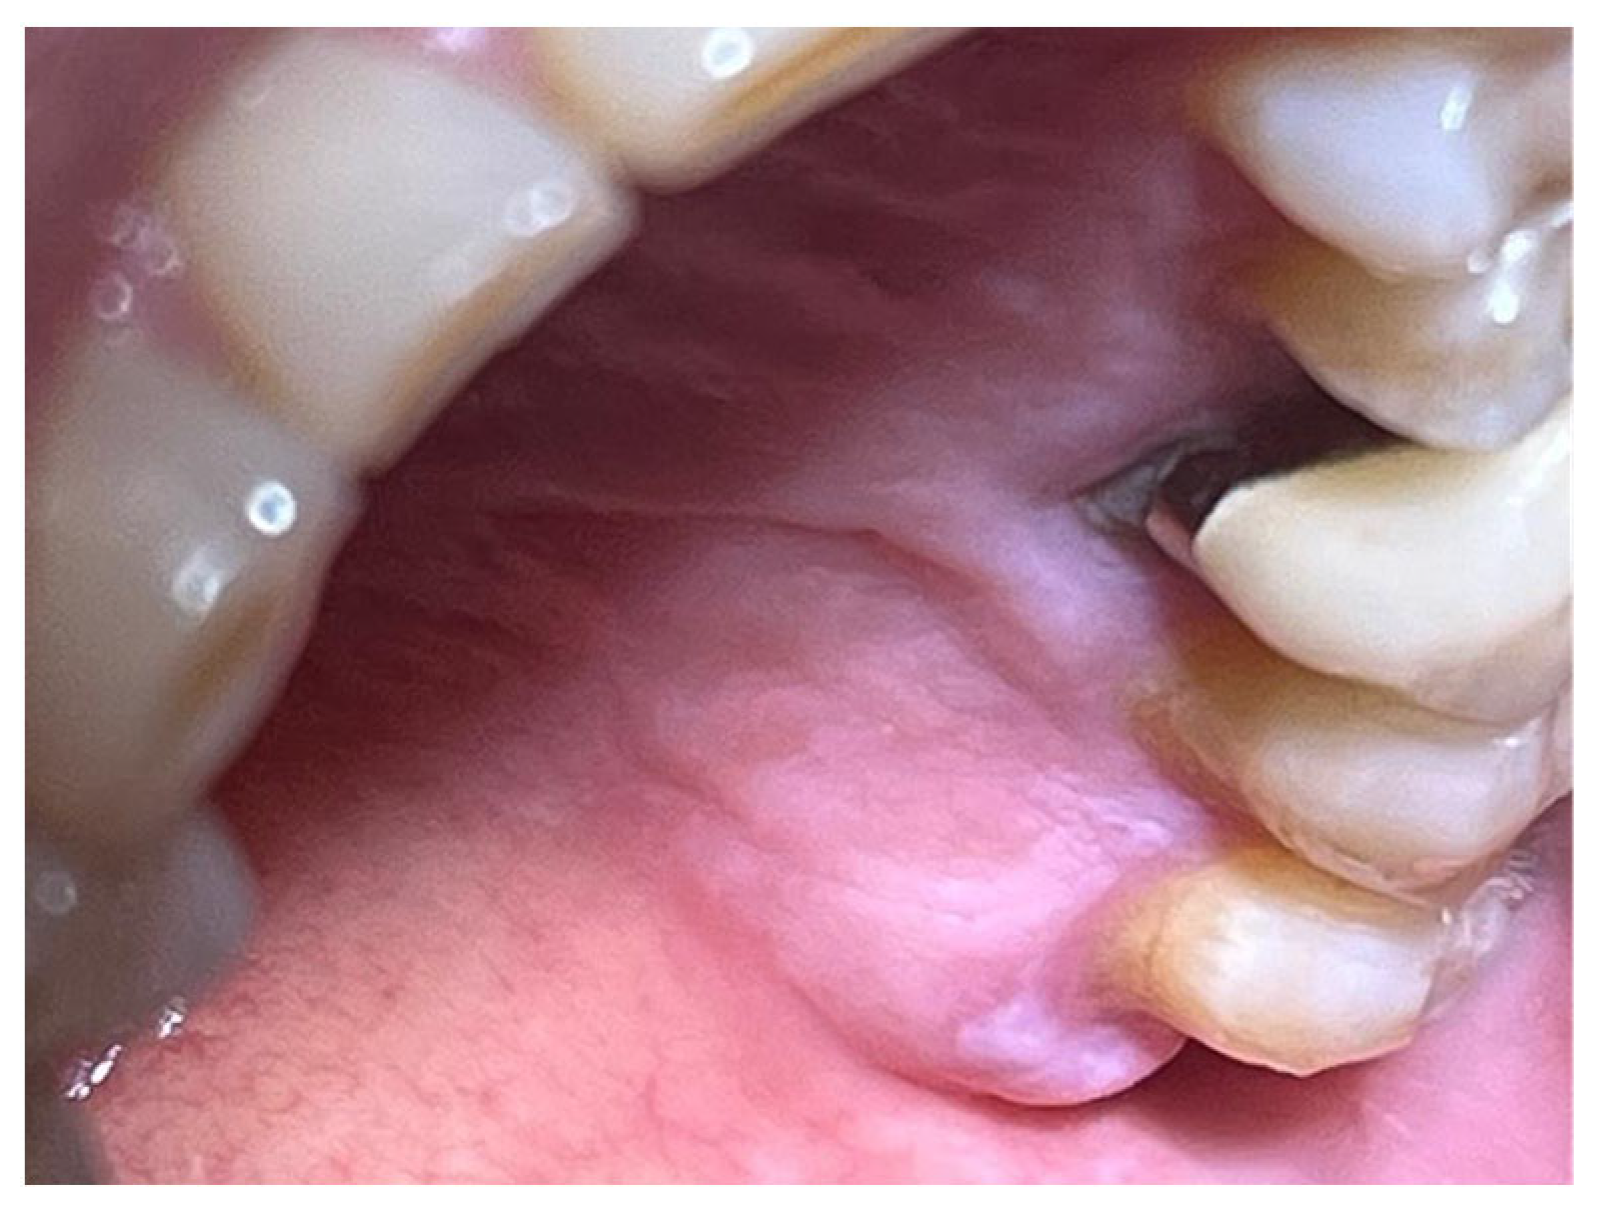

The study involved nine patients diagnosed with cardiovascular conditions, selected according to clearly defined inclusion criteria: presence of diagnosed cardiac conditions, the need for oral surgery, and signed informed consent. Exclusion criteria included patients with known allergies to the components of Glubran II, active infections, or systemic conditions contraindicating surgery. All patients were administered an antibiotic regimen consisting of Amoxicillin + Clavulanic Acid (875/125 mg), GlaxoSmithKlin, London, UK starting 24 h prior to the procedure, which was performed after obtaining cardiology clearance. Excellent results in terms of managing intra- and postoperative bleeding and tissue healing were observed in a 67-year-old patient with hypertension and diabetes mellitus, who underwent an excisional biopsy of a white lesion located on the palate with a leukoplakic appearance. The lesion, located on the palatal vault, appeared white, non-glossy, with undefined margins and soft consistency, and was non-removable via scraping biopsy (Figure 1 and Figure 2). A decision was made to surgically remove the lesion with wide incision margins to provide a biopsy sample (containing the lesion with surrounding healthy tissue) to the Department of Pathological Anatomy at the University Hospital of Rome Tor Vergata.

The patient was prepared for the surgical procedure with antibiotic therapy (Amoxicillin + Clavulanic Acid 875/125 mg) and 2% Chlorhexidine rinses starting the day before the surgery. Following the guidelines for patients with hypertension (Figure 1), the excision was performed with the complete removal of the lesion, adhering to standard surgical procedure techniques (Figure 3). Post-excision, hemostasis was achieved using Glubran II surgical glue. In this case, an endodontic needle was used for material application, allowing single droplets to be applied directly to the surgical site (Figure 4). Hemostasis was rapidly achieved in the areas where the glue was applied. The material was carefully deposited around the perimeter of the surgical site, ensuring individual droplets were placed without excessive application (Figure 5).

Figure 1. Lesion resembling leukoplakia localized on the palate, non-removable through biopsy by scraping.

Figure 2. Leukoplakia-like lesion localized on the palate following scraping with a sterile gauze.